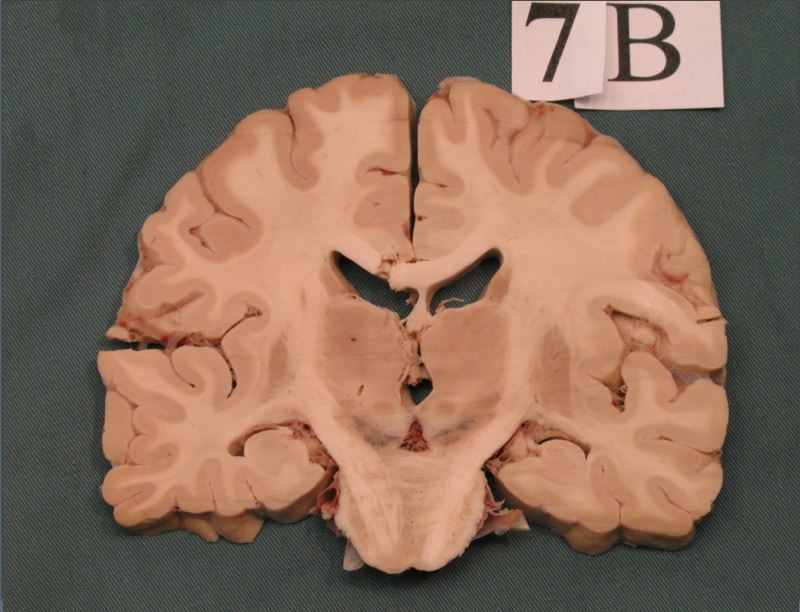

Note:

- white matter: so named because of the bright shiny appearance to the naked eye

- gray matter: so named because it is less bright, a little more dull looking. But nothing dull about it.

Common techniques to visualize brain structure

Note:

- Cell stain is Nissl stain

- Fiber stain is Luxol Fast blue